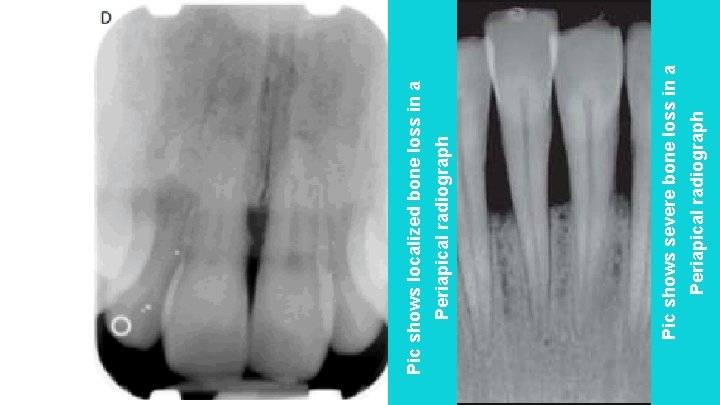

Periapical radiograph Pic shows severe bone loss in a Periapical radiograph Pic shows localized bone loss in a